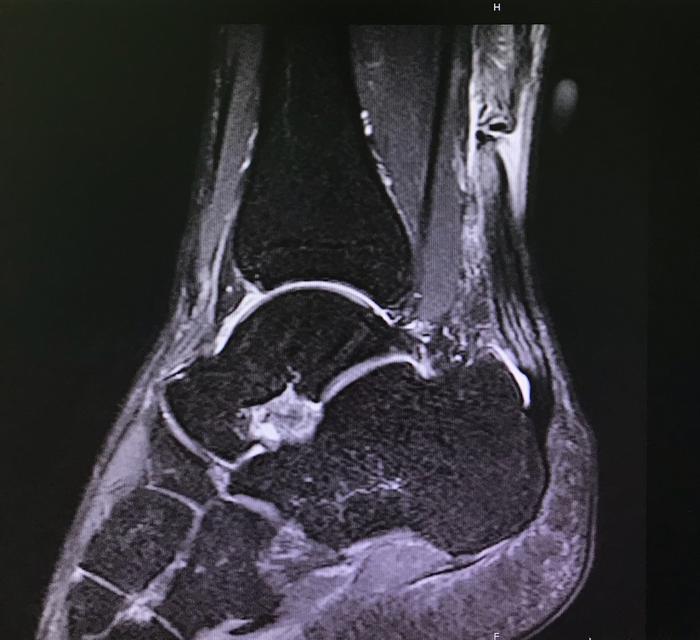

与x光片和ct比,磁共振图像跟腱显示清晰,呈连续带状低信号.